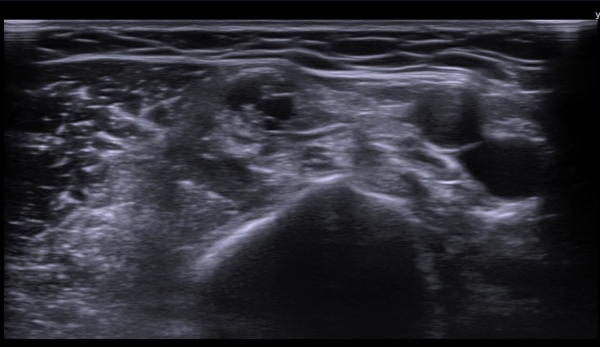

ÃÊÀ½ÆÄ  °Ë»ç  : À­ÆÈ ±ÙÀ§ºÎ Á¤Áß ½Å°æ Ⱦ´Ü¸é°Ë»ç¿¡¼­ Á¤Áß ½Å°æÀÇ ºÎÁ¾°ú ÀϺΠ½Å°æ¼¶À¯ÀÇ Àú¿¡ÄÚ ºÎÁ¾ÀÌ °üÂûµÈ´Ù

(»çÁø 1, 2). ŽÃËÀÚ¸¦ Á¶±Ù ´õ ±ÙÀ§ºÎ·Î À̵¿ÇÏ´Ï Á¤Á߽ŰæÀÇ Àú¿¡ÄÚ ºÎÁ¾ÀÌ °üÂûµÈ´Ù(»çÁø 3, 4).

Á¤Á߽Űæ Ⱦ´Ü¸é°Ë»ç¿¡¼­µµ Á¤Á߽ŰæÀÌ Àú¿¡ÄÚ ºÎÁ¾ÀÌ ±æ°Ô  °üÂûµÇ°í ½ÇÁú³» ƯÁ¤ ¼¶À¯¼ÒÀÇ

Àú¿¡ÄÚ ºÎÁ¾ÀÌ ¶Ñ·ÇÇÏ´Ù(»çÁø 5, 6).